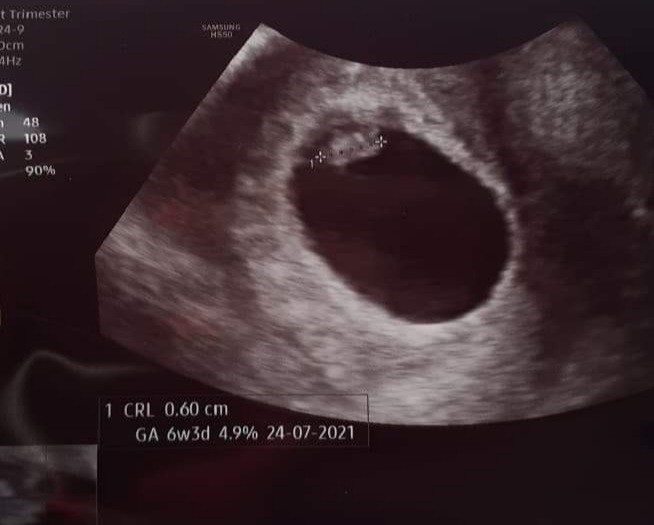

Czesc ciociunie , mam 0.6 cm i bijace serduszko 😍😍😍